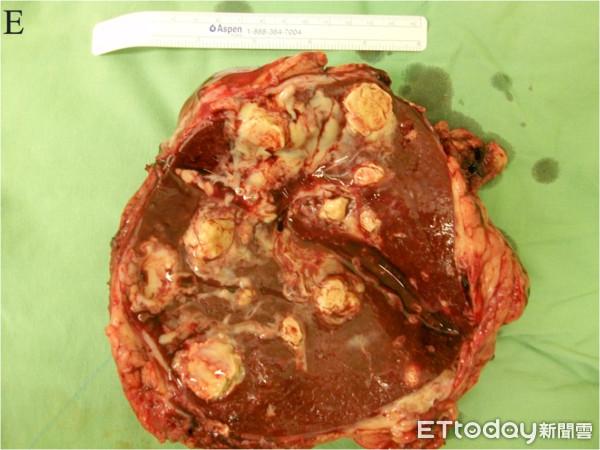

赤脚散步惹祸!他患类鼻疽胃狂喷白脓 割脾脏保命

图片尺寸600x450